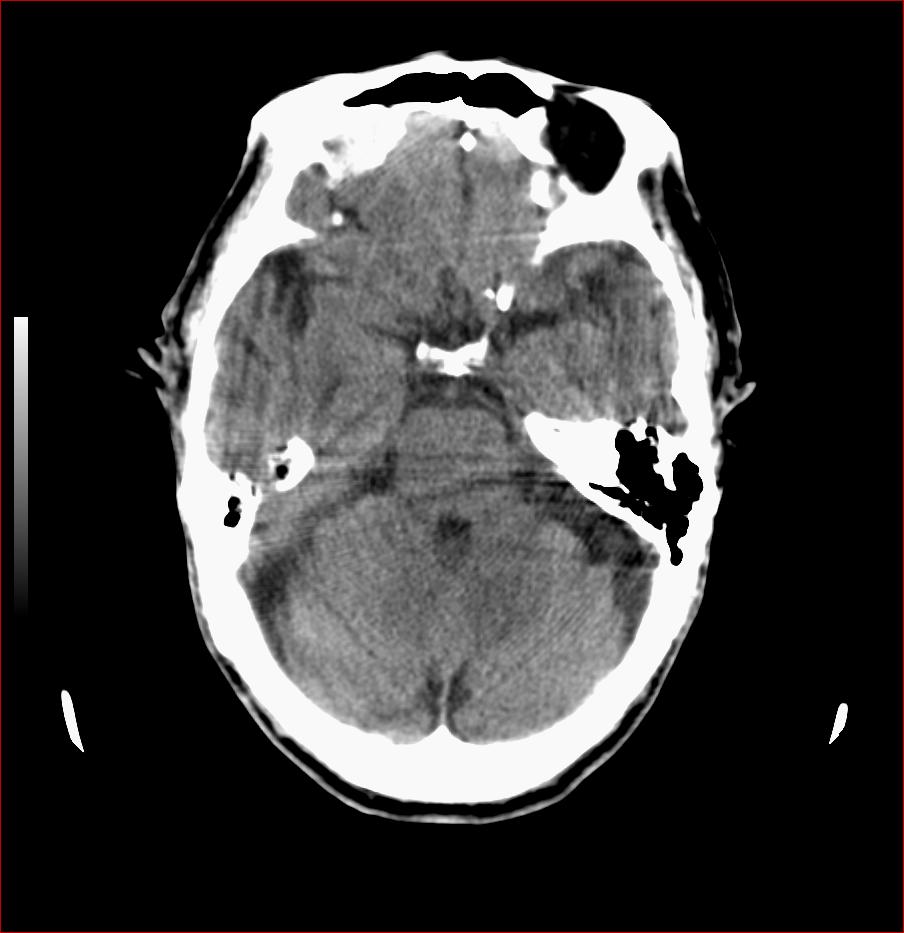

男,84岁,左下肢无力伴口角歪斜1天,血压160/80。请问一下双侧基底节区是脑梗塞吗?

右侧基底节区斑片状低密度影,边缘模糊,结合临床考虑:1.右侧基底节区脑梗塞;2.老年性脑改变。

1.两侧基底节区及右顶深部脑梗塞。2.右侧外囊区脑软化灶。3.脑萎缩。4.脑白质脱髓鞘改变。

右侧基底节区斑片状低密度影,边缘模糊,结合临床考虑:1.右侧基底节区脑梗塞;2.老年性脑改变

1.双基底节区及双顶深部脑梗塞;2.右外囊区软化灶;3.皮层下动脉硬化性脑病.

1 两侧基底节区脑梗塞;

2 右侧壳核区脑软化灶;

3 脑白质脱髓鞘;

4 脑萎缩。